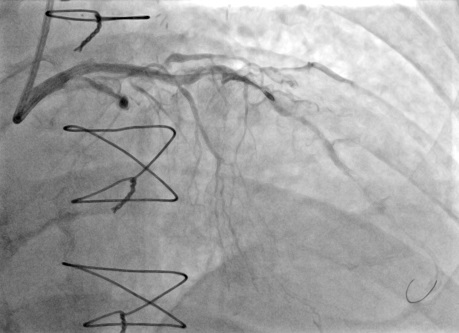

He was referred for PCI, however, despite maximizing support with a guide catheter extension, the mid-LAD could not be crossed even with 1.0-mm balloons. Rotational atherectomy was performed with a 1.5-mm Rotablator burr over a Rota-Floppy guidewire (Boston Scientific) at 160 000 rpm, causing ST-segment elevation due to no reflow. After successful treatment of no reflow with aspiration through a Penumbra catheter and administration of intracoronary nicardipine and adenosine, repeat rotational atherectomy was performed and the LAD lesions were successfully crossed. Upon withdrawal, the burr became entrapped in the mid-LAD within a stented segment (Figure 2, Video 2). Removing the burr by pulling on Dynaglide mode was not successful. We cut the shaft of the burr and advanced a guide catheter extension over the burr into the mid-LAD (Video 3). After multiple attempts and pulling the guidewire, we were able to remove the entrapped burr (Video 4). The burr was covered by stent fragments (Figure 3).

The patient remained stable and repeat angiography showed no evidence of dissection or perforation. Intravascular imaging showed severely calcified neoatherosclerosis. Angioplasty with intravascular lithotripsy and noncompliant balloons was then performed with an excellent result (Figure 4, Video 5).